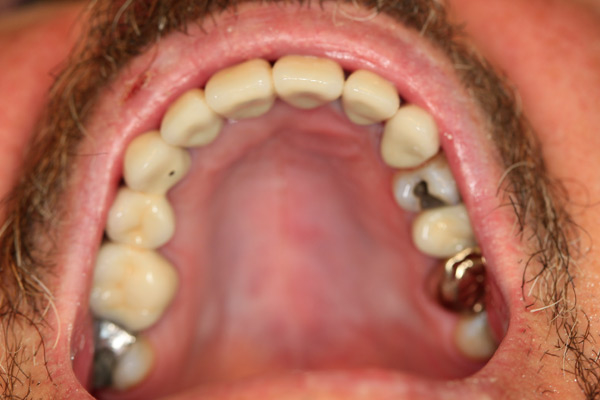

Case Study 3

Problem: This gentleman had an accident with a four-wheeler which gave him multiple jaw fractures and broken teeth. As a result of his accident, it left him with no teeth in the upper and lower front.

Plan: Our plan… the fractures were fixed and three implants were placed on the upper arch and two implants on the lower arch bridging the missing teeth. We also fixed a few broken teeth with root canals and crowns.

Don’t let accidents ruin your smile.